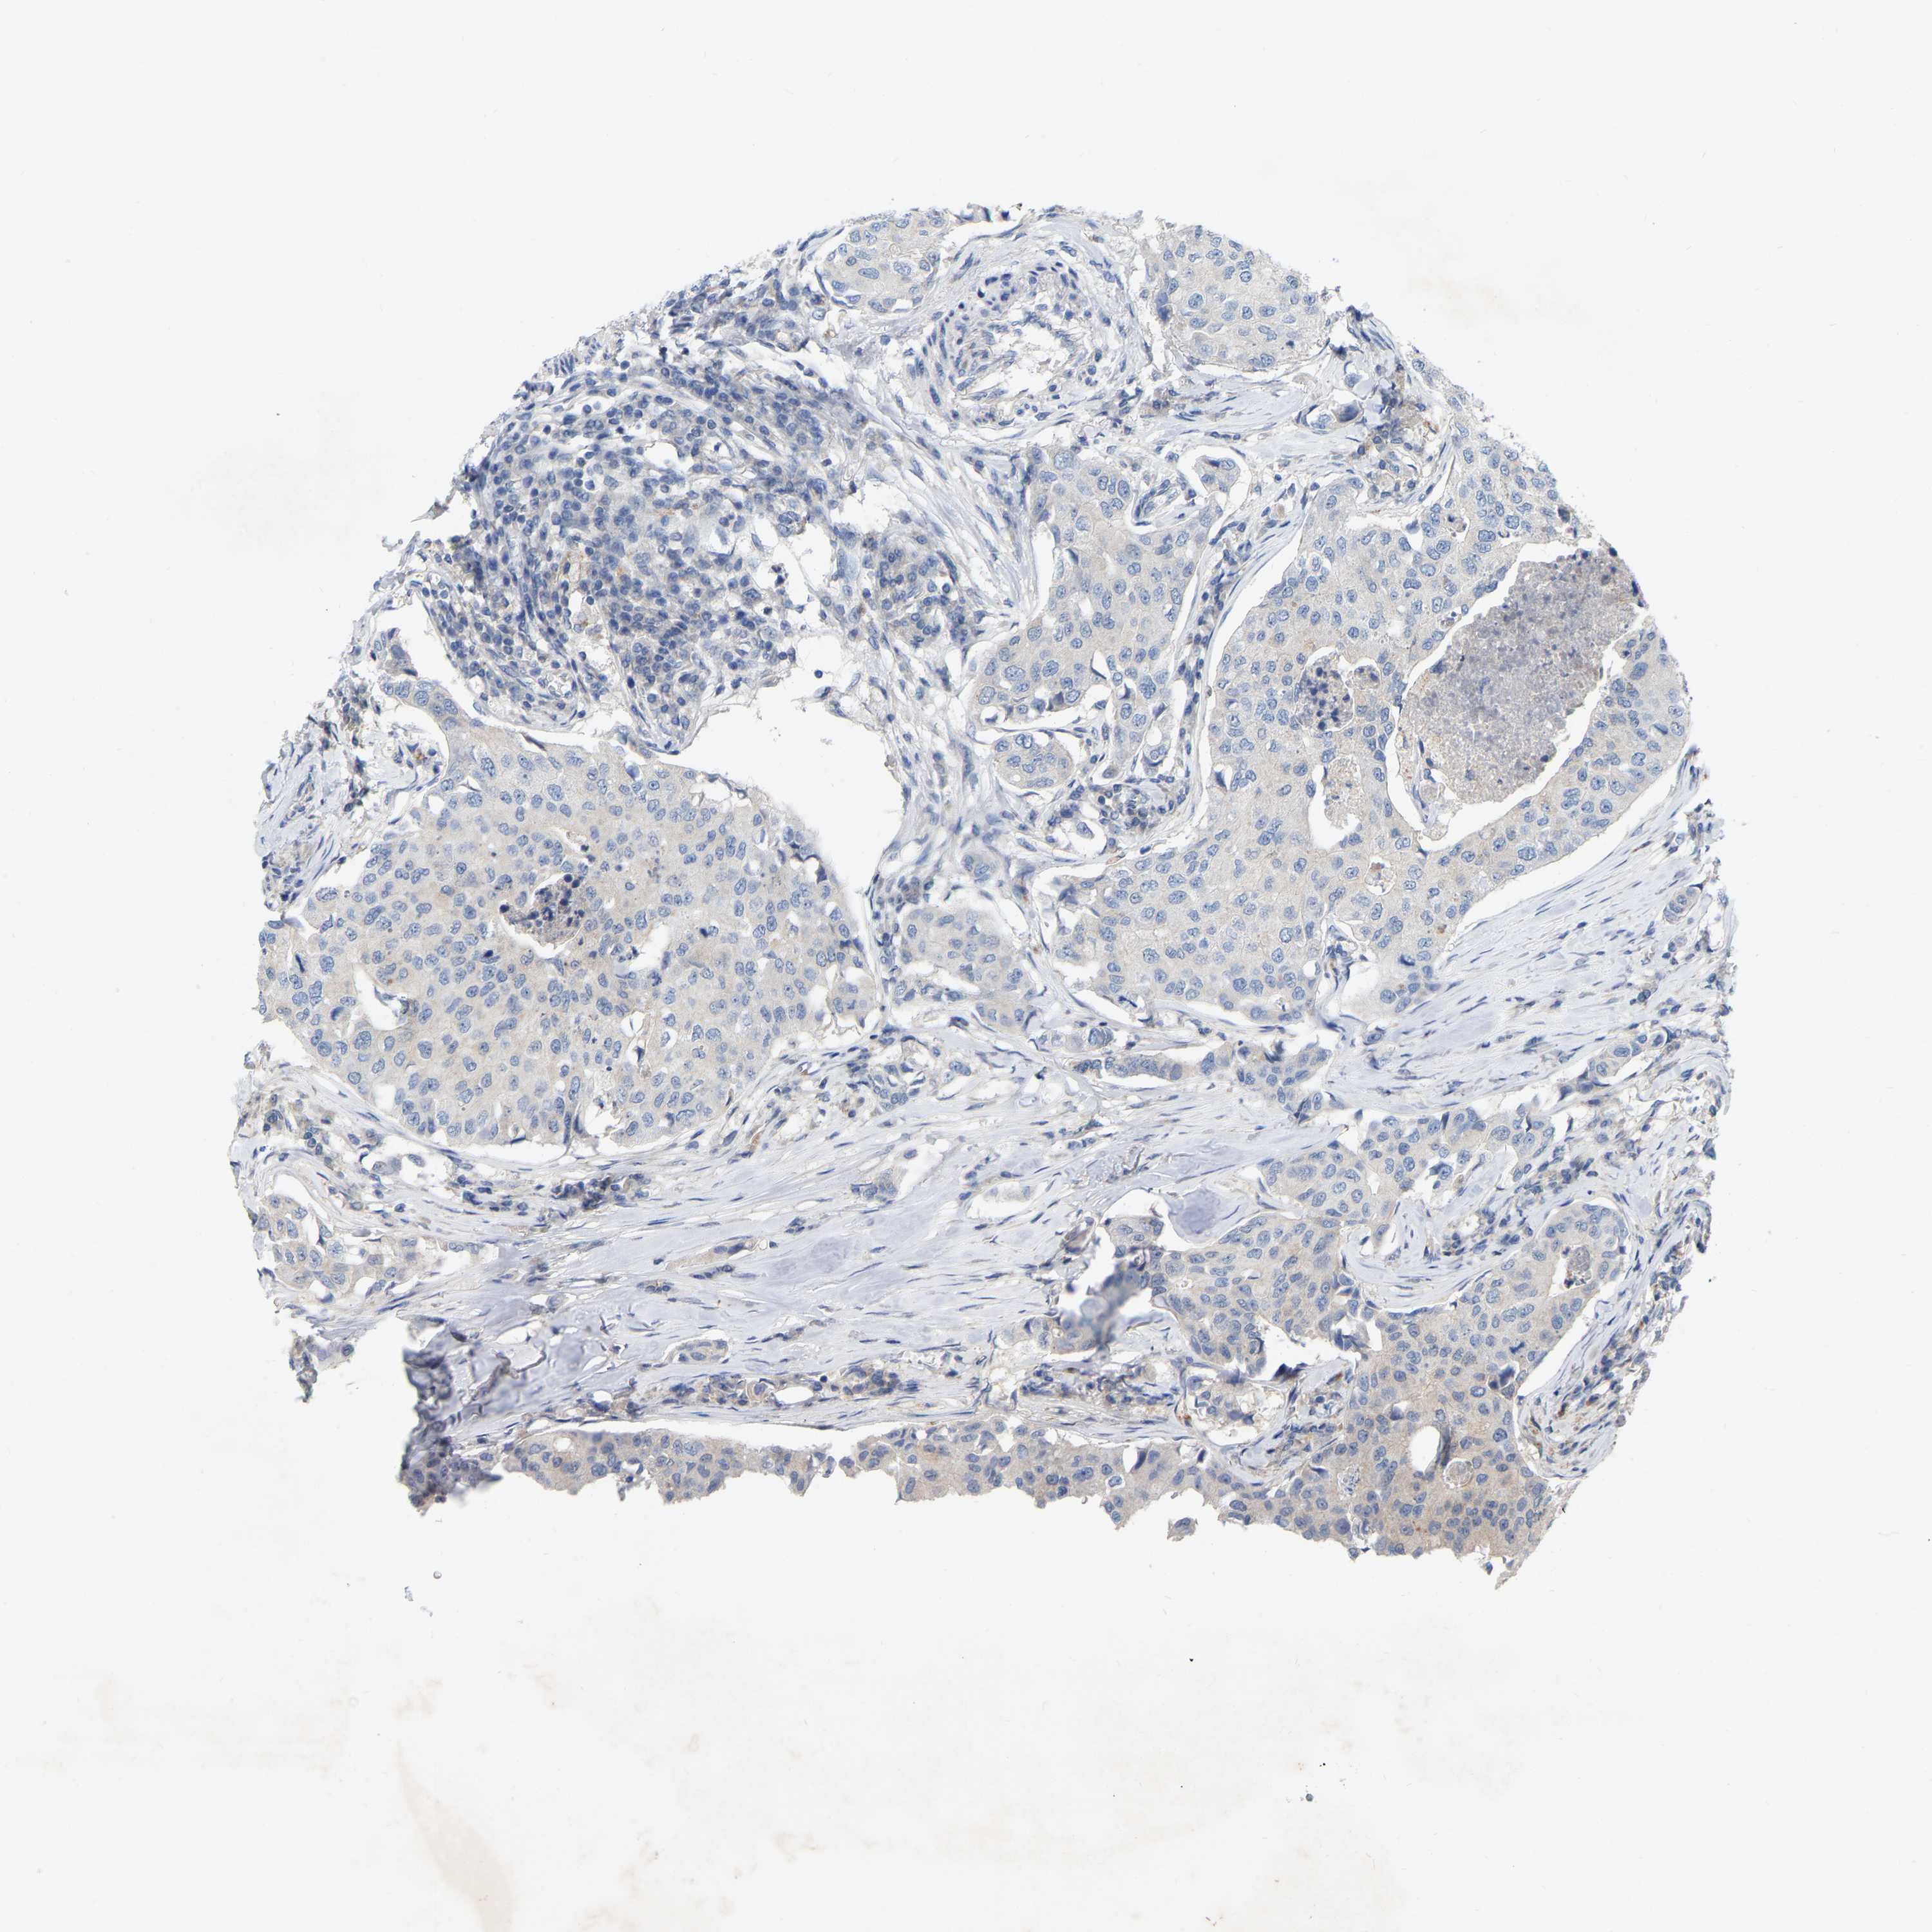

CANCER BREAST CANCER Show tissue menu

BRCA TCGA BRCA VALIDATION PROTEIN EXPRESSION